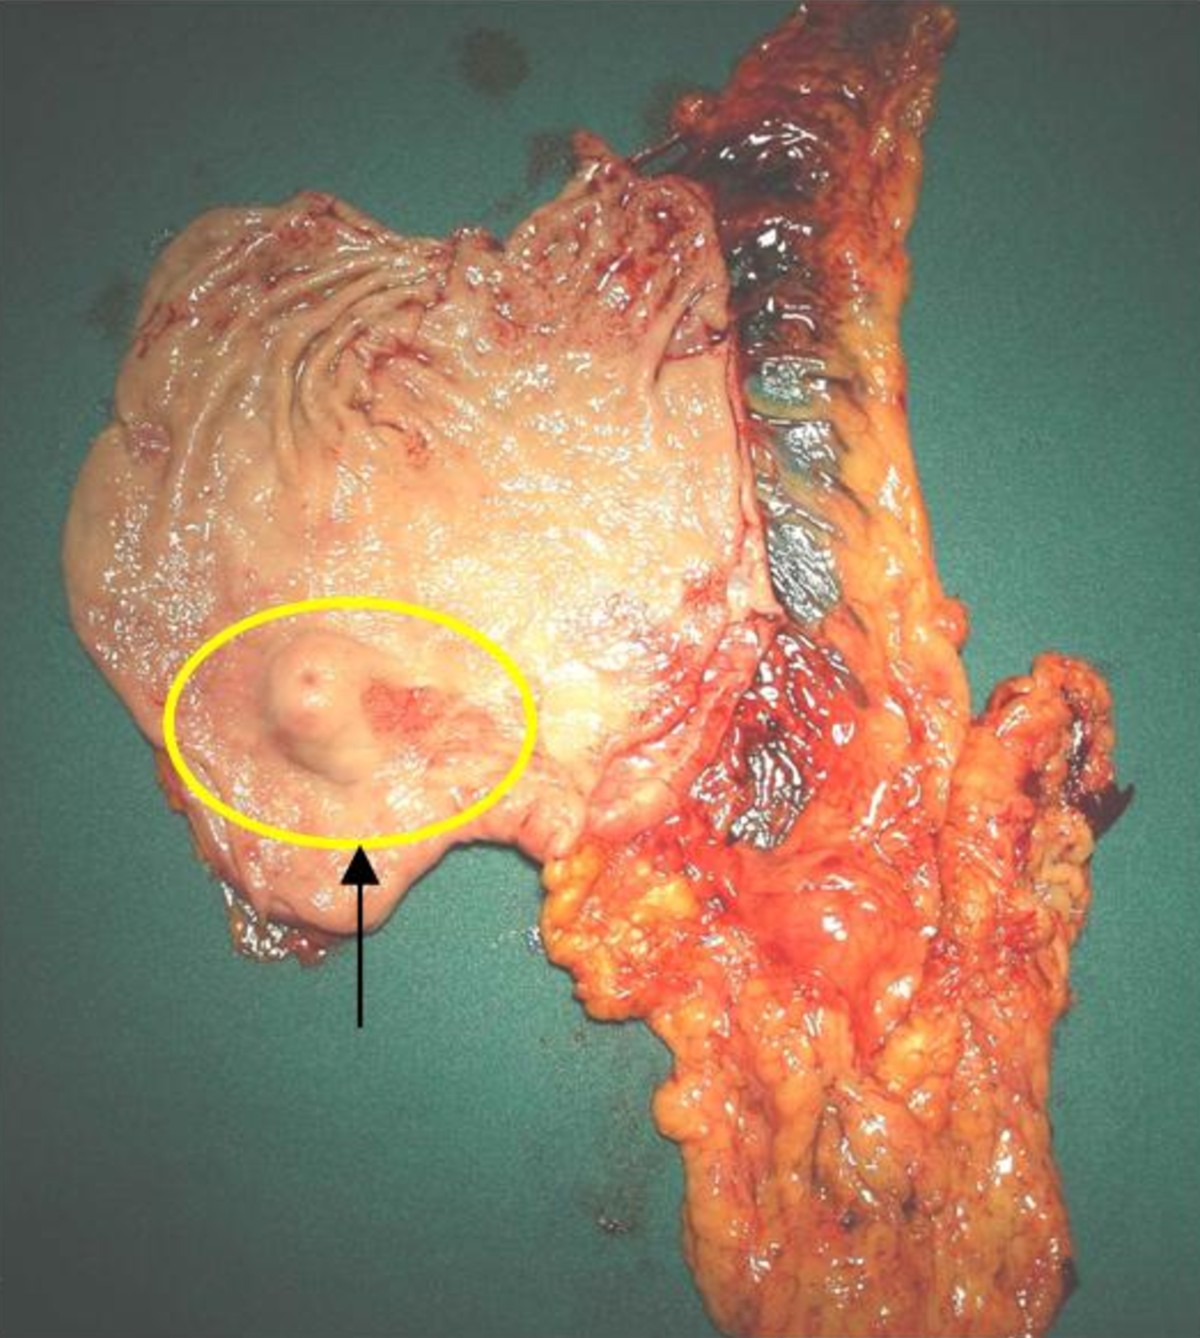

Gastric Glomus Tumor: A Case Report | World Journal Of Surgical

Gastric glomus tumor: A case report | World Journal of Surgical wjso.biomedcentral.com

tumor gastric stomach glomus figure case report mass